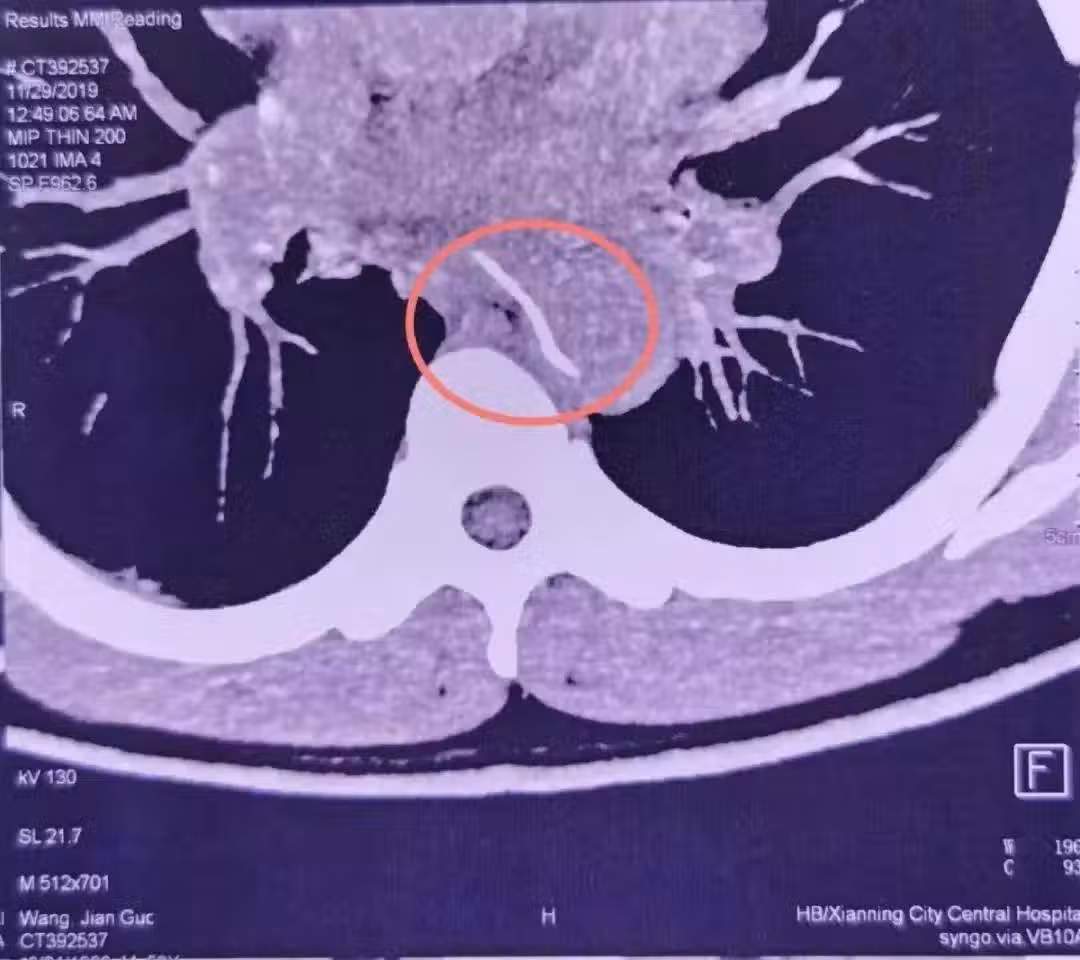

胸主動脈,作為人體最粗大的動脈血管,血管壓力很高,如果形成破口,出血就會呈噴射狀。這個場景就好比「大壩決堤」,幾乎沒有搶救的機會。

就算醫生再見多識廣,也會覺得這很罕見,甚至一開始以為裡面的是塑料牙籤。畢竟這麼長、這麼尖的魚刺,人怎麼能吞得下去呢?